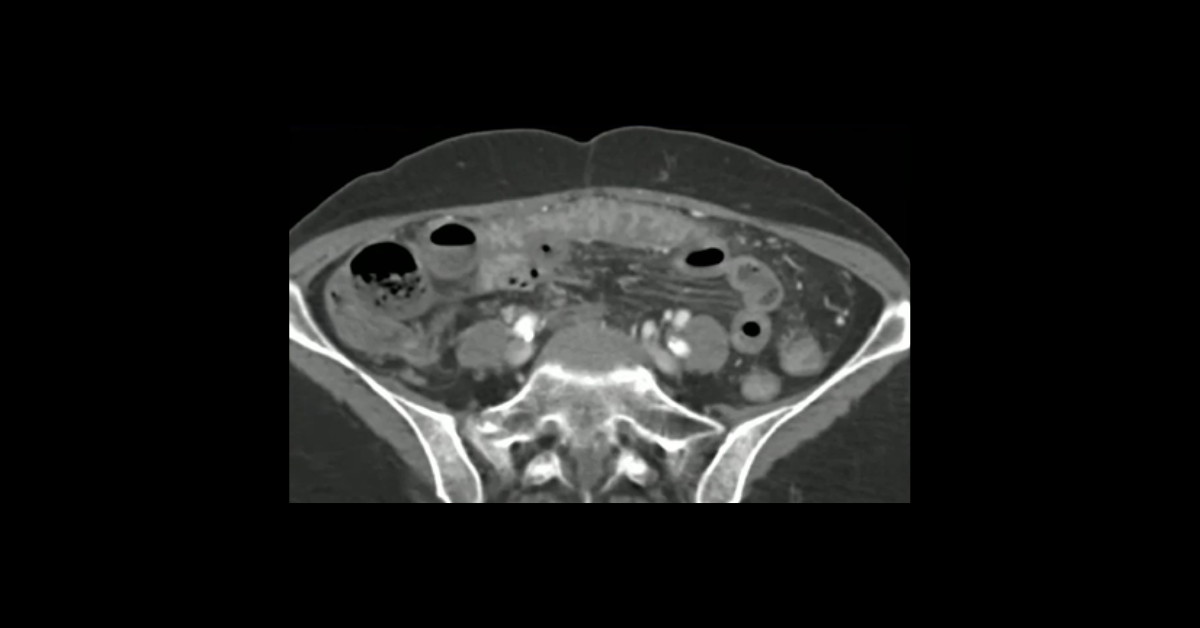

Presented by Vincent Mellnick, MD at Practical Radiology 2025. The upper gastrointestinal tract can be oft-overlooked site of disease in the emergency department patient, but is frequently be the site of pathology, including inflammation/infection, ischemia, obstruction, perforation, and hemorrhage. This talk will discuss common (and some uncommon) conditions causing these presentations in the esophagus, stomach, and duodenum, with emphasis on CT findings.